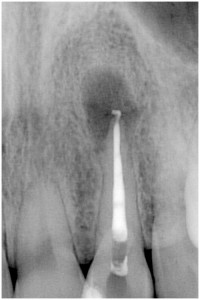

歯髄壊死 左上の前歯 川口の歯科 歯医者 さかえ歯科クリニック

2014年12月16日

術 前 術 後